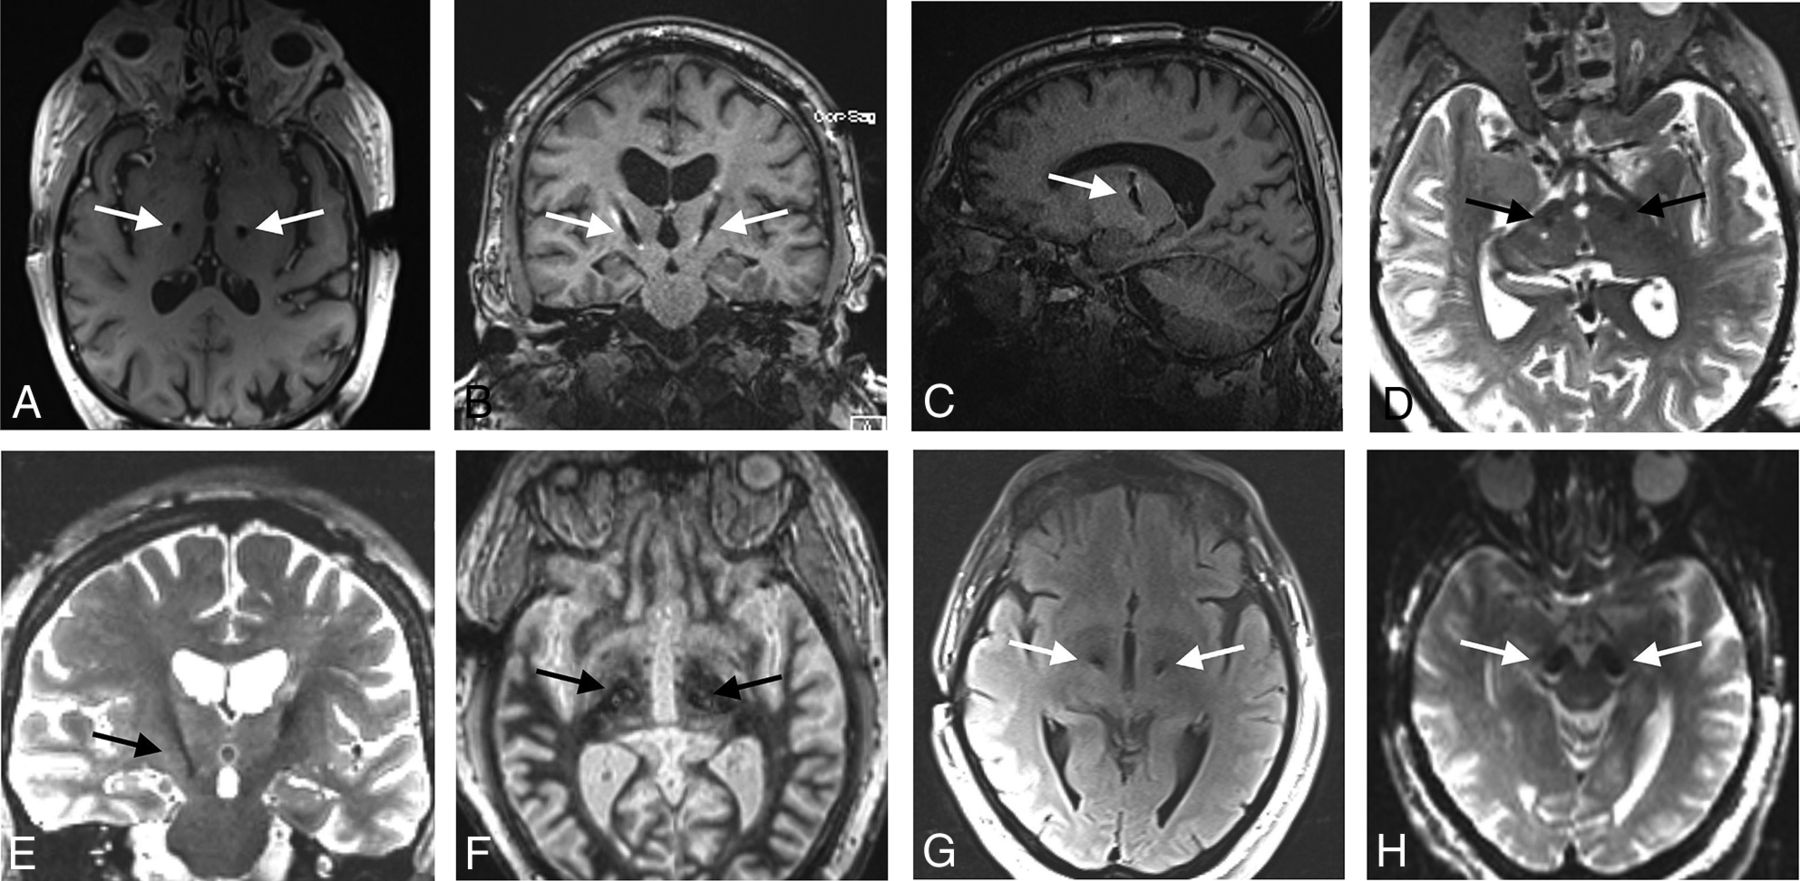

Imaging artifacts, although not a specific object of analysis in this study, were noted to be large, as is common with DBS electrodes under MR imaging. These were not used to determine stereotactic accuracy. Examples of electrode artifacts are shown in Fig 2.

Examples of the MRI artifacts of implanted Infinity DBS electrodes. The largest artifacts were seen in T1 images (A–C) and the smallest artifacts on T2 images (D, E). Artifacts on WMn (F), FLAIR (G), and DWI (H) sequences are also shown. Arrows indicate electrodes.